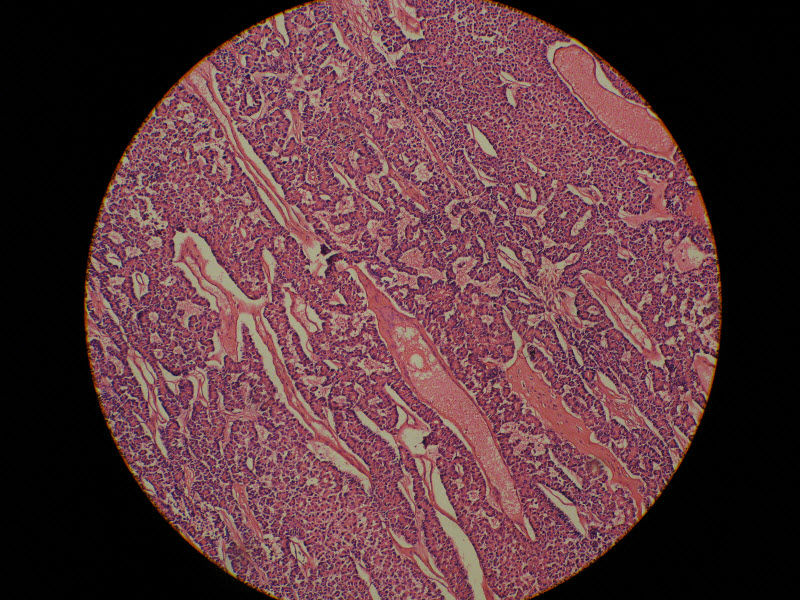

肾脏肿瘤,请教诊断!图4

名称:图4

描述:20倍

肾脏肿瘤,请教诊断!图5

名称:图5

描述:40倍